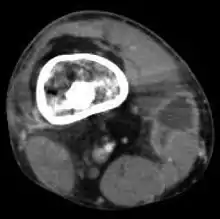

Radiographs and CT are the initial method of diagnosis, but are not sensitive and only moderately specific for the diagnosis. They can show the cortical destruction of advanced osteomyelitis, but can miss nascent or indolent diagnoses.[23]

Confirmation is most often by MRI. The presence of edema, diagnosed as increased signal on T2 sequences, is sensitive, but not specific, as edema can occur in reaction to adjacent cellulitis. Confirmation of bony marrow and cortical destruction by viewing the T1 sequences significantly increases specificity. The administration of intravenous gadolinium-based contrast enhances specificity further. In certain situations, such as severe Charcot arthropathy, diagnosis with MRI is still difficult.[23] Similarly, it is limited in distinguishing avascular necrosis from osteomyelitis in sickle cell anemia.[24]